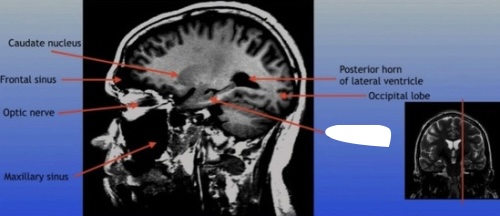

Caudate Nucleus

A C-shaped structure within the brain's basal ganglia, involved in various functions including motor control and learning.

Frontal Sinus

A paired cavity located within the frontal bone, above the eyes, that plays a role in sinus drainage and resonance of the voice.

Optic Nerve

The bundle of nerve fibers that transmits visual information from the retina to the brain. It plays a crucial role in the sense of sight.

Maxillary Sinus

A paired cavity located within the maxilla, situated below the eyes, that contributes to sinus drainage and helps lighten the weight of the skull.

Posterior Horn of Lateral Ventricle

The posterior part of the lateral ventricle, involved in the production and circulation of cerebrospinal fluid within the brain.